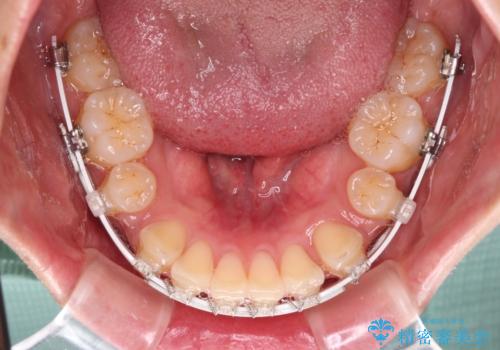

- 矯正装置

- 審美装置

- 前歯の突出感を気にして来院された患者様です。

咬合力が非常に強く、咬合力で前歯が前方に押し広げられており、上下唇に閉じにくさが認められました。

上下左右の第一小臼歯4本を抜歯し、ワイヤー装置にて矯正治療を行うこととしました。

強い咬合力により前歯の隙間がなかなか閉じられず、治療期間は長いものとなりましたが、横顔の印象が大きく変わるほど口元の印象を改善することができました。